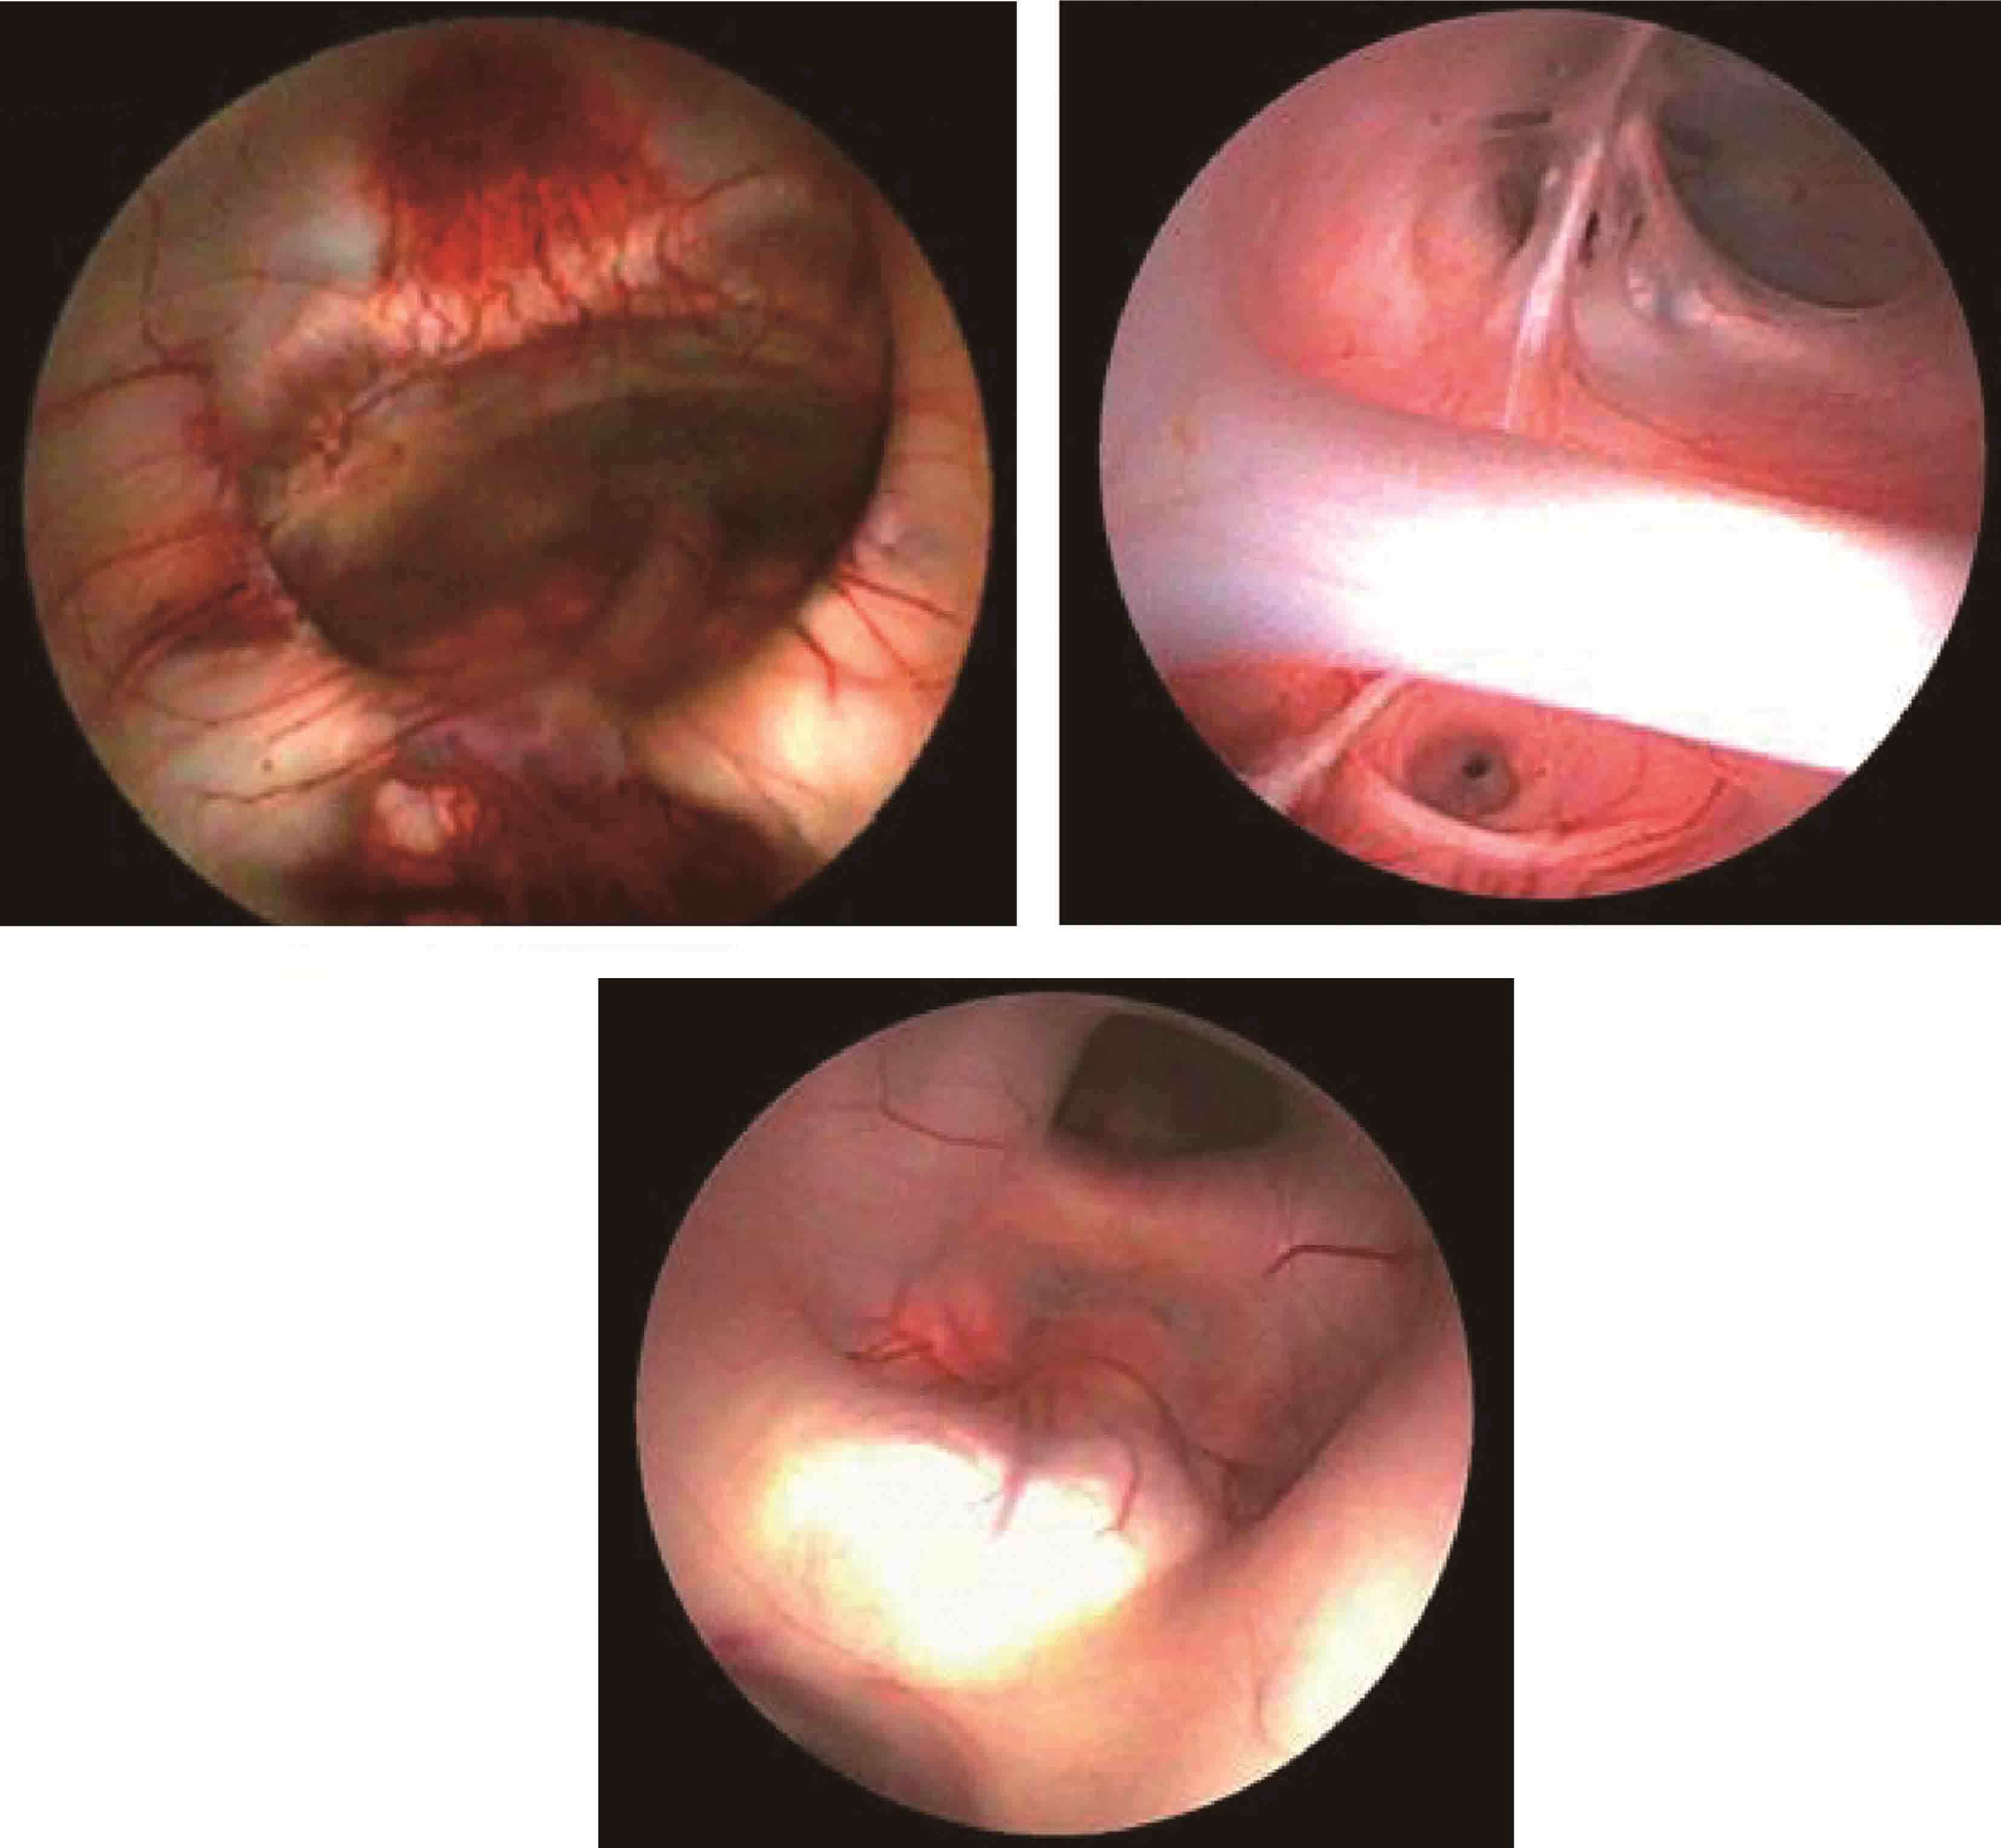

11.蛛网膜囊肿相关性脑积水的内镜治疗 蛛网膜囊肿相关性脑积水(hydrocephalus associated with arachnid cyst)的最佳治疗,是一次性同时解决囊肿和积水问题。如不能同时解决,应首先处理囊肿,禁忌单纯行脑室腹腔分流术,否则会加速囊肿增大(图3-1-2-12)。内镜下微创手术治疗,可为多数患者一次性处理囊肿和积水(图3-1-2-13)。

图3-1-2-12 蛛网膜囊肿相关性脑积

a.脑积水合并中颅窝蛛网膜囊肿及鞍上池囊肿;b.分流手术后囊肿明显增大,中线移位;c.内镜下探查见囊肿突入侧脑室;d.内镜下脑室-脑池-囊肿造瘘术,清晰显示基底池

图3-1-2-13 蛛网膜囊肿相关性脑积

a.MRI轴位片显示脑积水合并双侧颅中窝蛛网膜囊肿;b.脑积水合并双侧颅中窝蛛网膜囊肿冠状位MRI所见;c~e.内镜下第三脑室底造瘘,双侧颅中窝蛛网膜囊肿-基底池造瘘